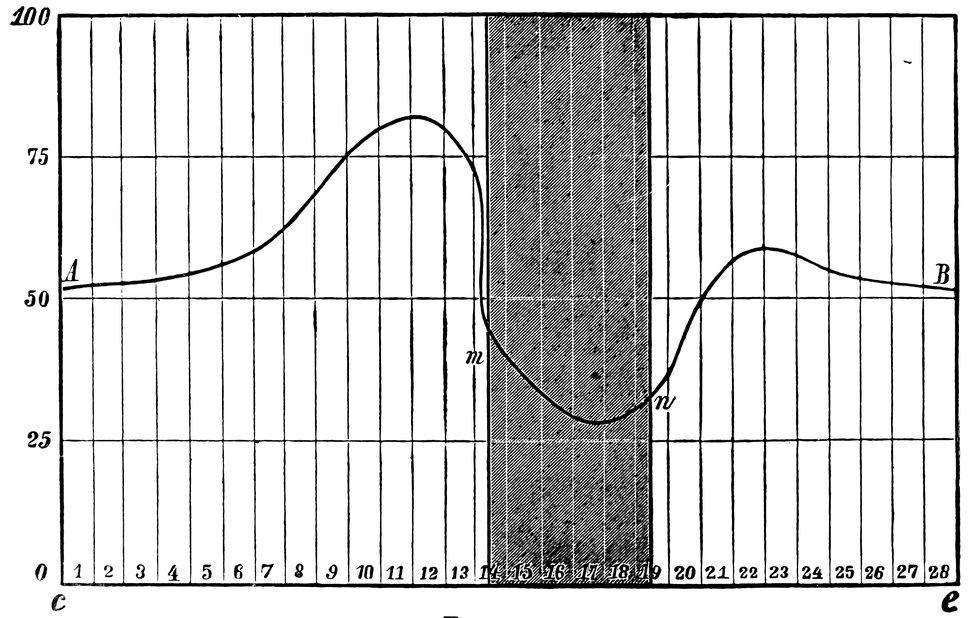

| 6. | Curve of rhythmical variations | 20 |

20Von Ott found in thirteen cases out of fourteen that at the beginning of the catamenial discharge or just before a considerable fall in blood-pressure occurred, and that throughout the flow the pressure almost always remained below the mean, no rise taking place till menstruation was finished; this fall in blood-pressure during menstruation was more considerable than could be accounted for by the moderate hæmorrhage. The same author, in conjunction with Schichareff, examined fifty-seven healthy women in respect of heat-radiation, muscular power, respiratory capacity, expiratory and inspiratory power, and tendon-reflexes. He found that the energy of the functions of the female body increased before the beginning of menstruation, but declined with or immediately before the appearance of the catamenial discharge. He exhibited this rhythmical variation in the vital processes by means of the following curve, in which the line A B represents these physiological variations, whilst on the abscissa line c e, the days of observation are recorded, and the interval m n represents the menstrual period. The degree of intensity of the united functions is indicated by the numbers 0–100 on the ordinate.

Fig. 6.